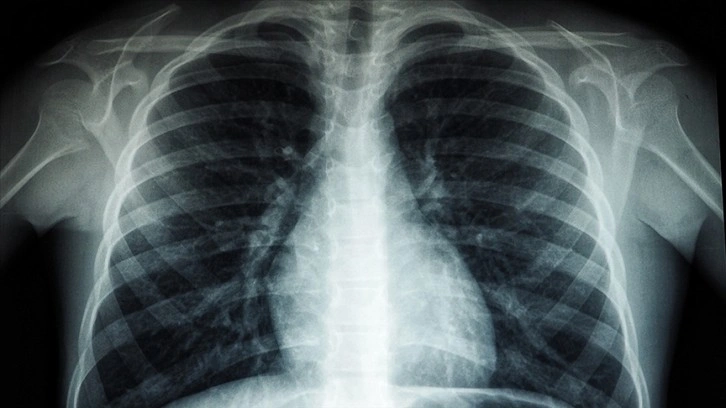

Röntgen ve ileri tetkiklerle hastalığın tespit edilebildiğinin altını çizen Özkara, Türkiye'de veremin 6 ay kullanılan ilaçlarla kolaylıkla tedavi edilebildiğine ve tüm tedavi masraflarının da devlet tarafından karşılandığına dikkati çekti.